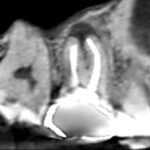

抜歯を避けるべく、精密根管治療を行いました。画像は根管充填のレントゲン写真です。第二小臼歯と第一大臼歯共に根の先までしっかり根管充填できました。